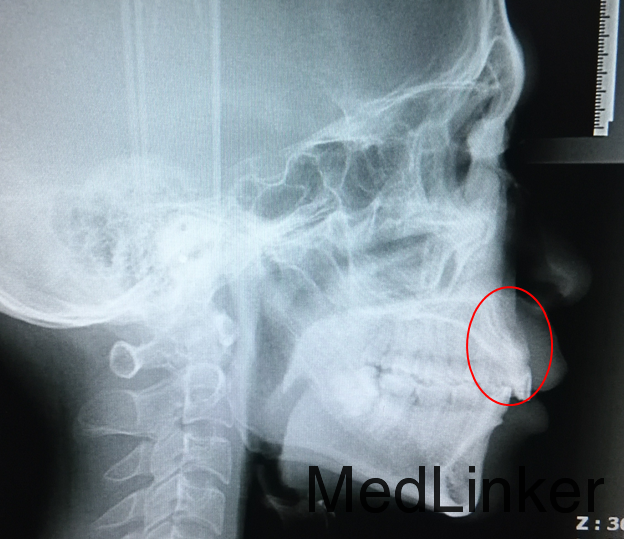

治疗:暂停关间隙,尽快恢复患者上前牙唇倾度,于澳丝上排齐上牙列的同时弯制门形曲改善上前牙转矩,将穿出骨皮质外的A1牙根压入牙槽骨内,矫治后侧位片可见上前牙牙根已回到骨皮质内,直立在牙槽骨中,上前牙冷热敏感症状消失。矫治历时1年9个月。

此病例给我们大家提了一个醒,在关闭间隙的时候一定要控制上前牙的转矩,否则会导致间隙无法关闭,覆合越来越深,如果继续关闭会出现像这个病例一样的骨开窗骨开裂,幸好此病人及时转诊,穿出的牙根尖只是突破了骨皮质,还尚未突破骨膜,若突破骨膜则估计无法挽救。